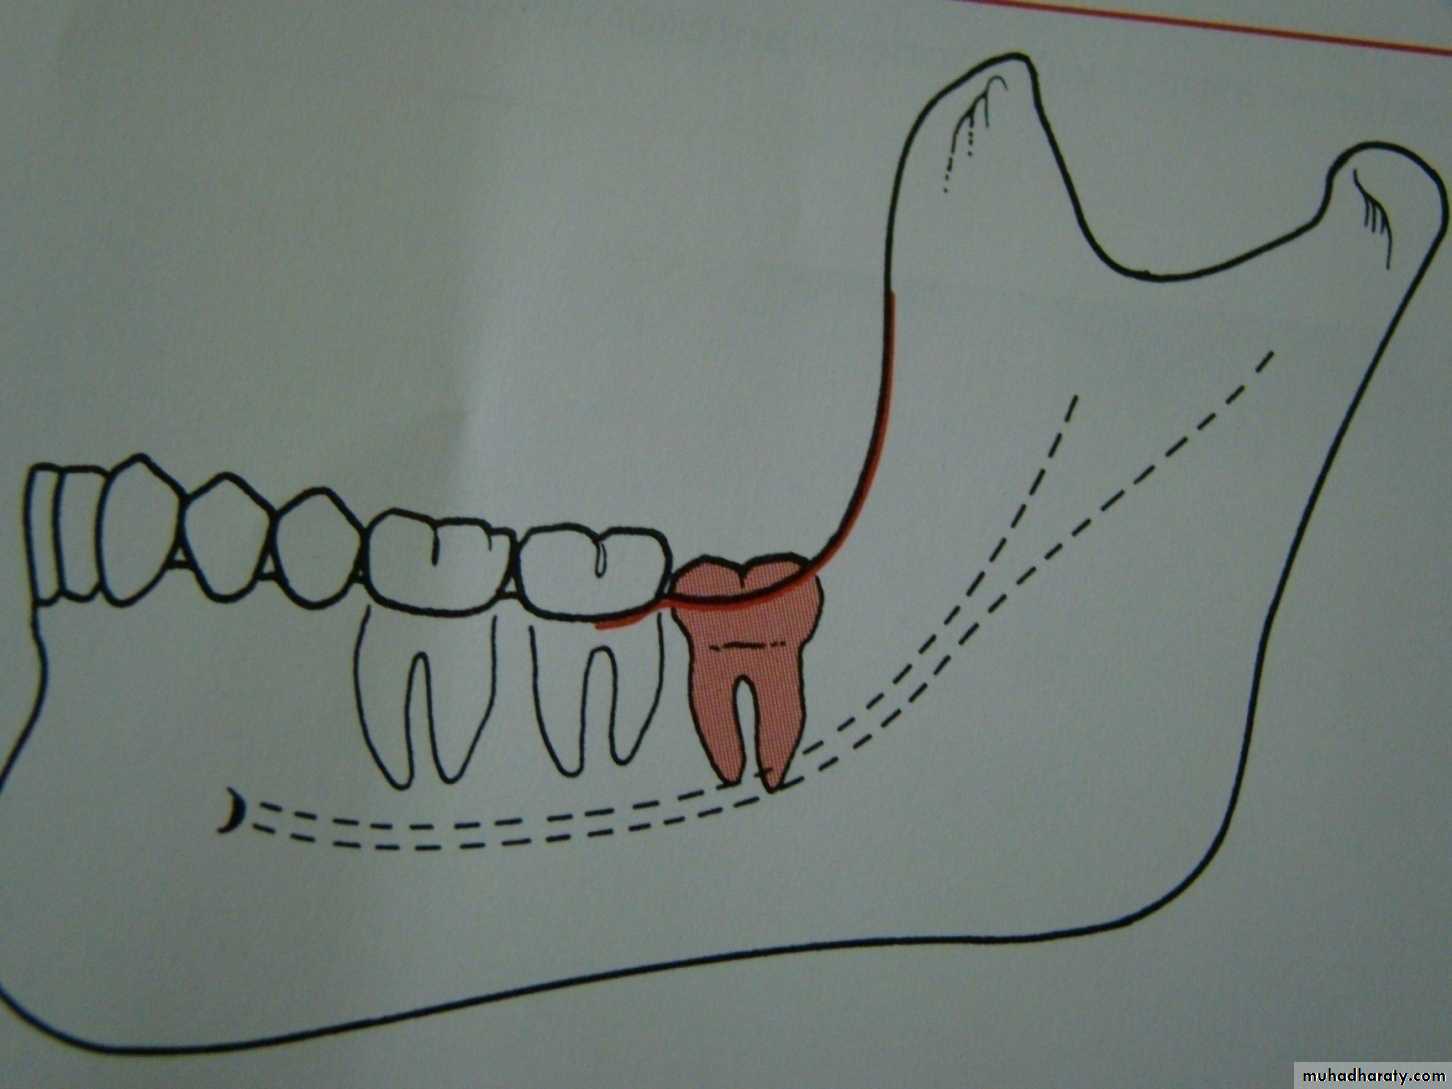

Winters classification of impacted lower third molarMesio angular

Disto angular

Horizontal

Vertical

Inverted

Transverse

Buccoversion

Linguversion